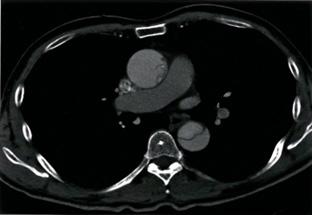

Tomografía computarizada (TC) del tórax

♦ En pacientes hemodinamicamente estables

♦ Confirma el diagnóstico → prueba de elección

♦ Permite clasificar en grados:

– Tipo I: desgarro de la íntima

– Tipo II: hematoma intramural

– Tipo III: pseudoaneurisma

– Tipo IV: ruptura (Hematoma periaórtico, ruptura libre)